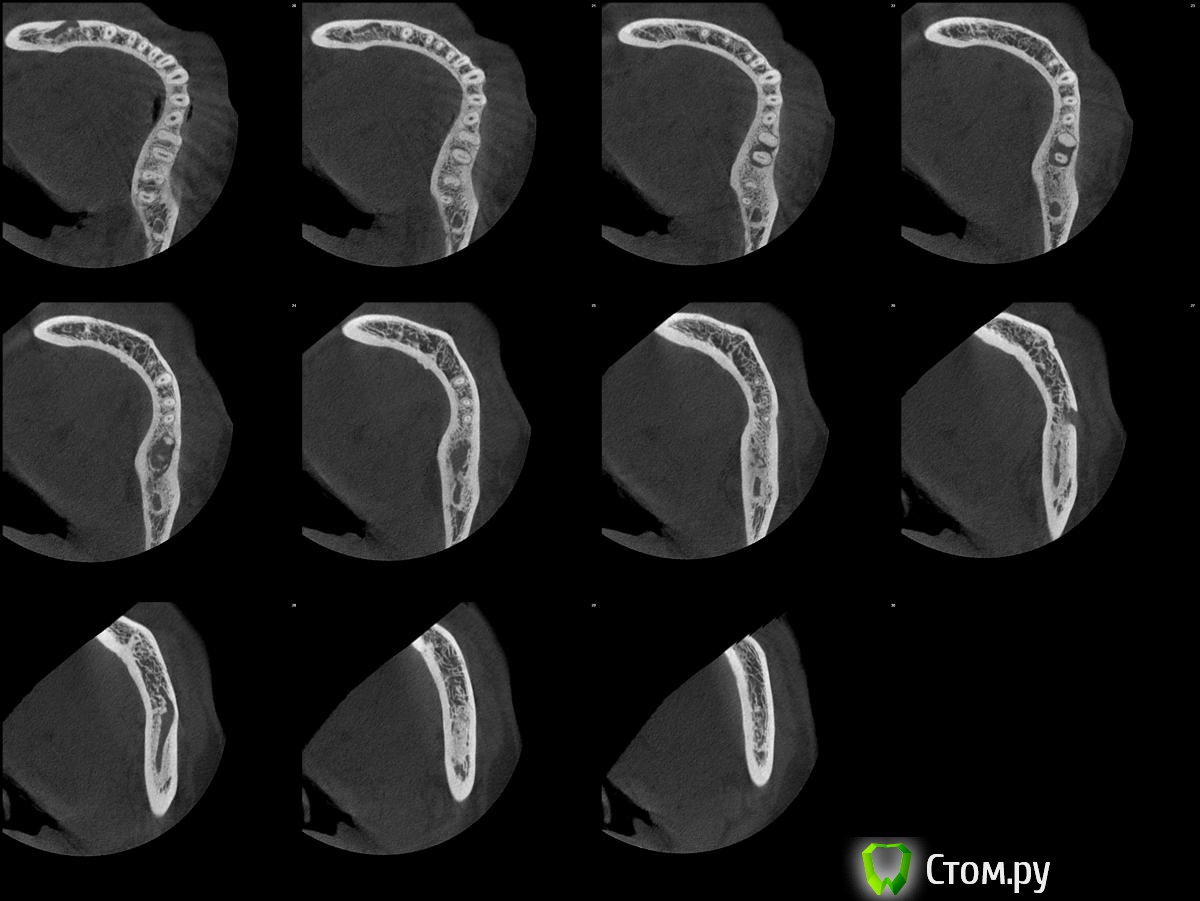

Kolchanov Опубликовано 29 декабря, 2013 Поделиться Опубликовано 29 декабря, 2013 эндо с резекцией верхушки медиального корня 3.7 Ваш коллега реально на столько крут, чтобы отчекрыжить верхушку корня у нижней семерки? Нет ли аксиальной нарезки этой области. Просто поглазеть на то, какую работу по кости ему придется сделать Ссылка на комментарий

turlih) Опубликовано 29 декабря, 2013 Автор Поделиться Опубликовано 29 декабря, 2013 Ваш коллега реально на столько крут, чтобы отчекрыжить верхушку корня у нижней семерки? Нет ли аксиальной нарезки этой области. Просто поглазеть на то, какую работу по кости ему придется сделать 1 Ссылка на комментарий

Kolchanov Опубликовано 29 декабря, 2013 Поделиться Опубликовано 29 декабря, 2013 Прикрепленные изображения Спасибо! Нармальна! Кидайте ссылку на тему лекарю Ссылка на комментарий